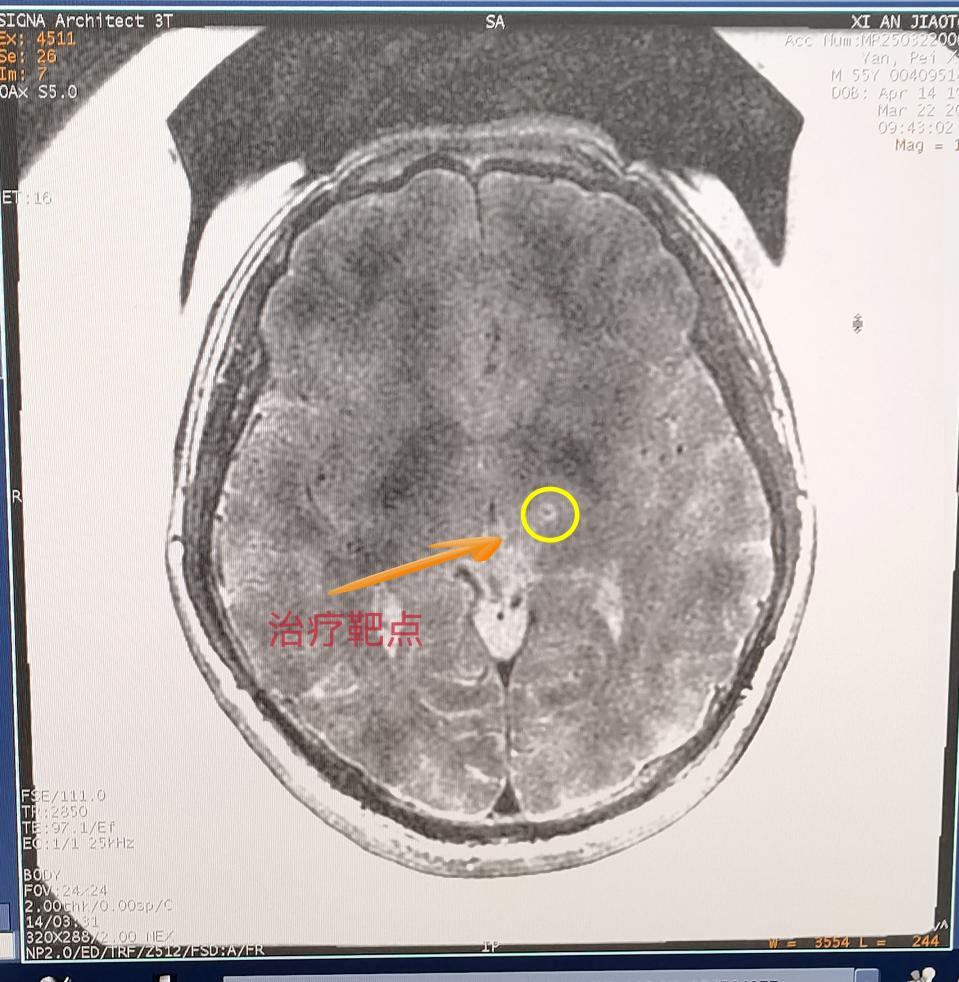

交大一附院神經(jīng)外科陳偉教授從病例出發(fā),詳細(xì)向大家講述了磁波刀技術(shù)原理,分享應(yīng)用案例并展示治療效果。

這項革命性技術(shù)融合了磁共振導(dǎo)航與聚焦超聲技術(shù),通過高精度磁共振鎖定腦內(nèi)異常神經(jīng)靶點,運用聚焦超聲波束穿透顱骨實施靶點高溫消融,從而阻斷震顫信號傳導(dǎo)。整個過程無需開顱,真正創(chuàng)造出“隔山打?!钡尼t(yī)學(xué)奇跡。在治療過程中,閆先生在清醒狀態(tài)下躺入磁共振室,在醫(yī)生的嚴(yán)密監(jiān)護(hù)下,陳偉醫(yī)生通過最先進(jìn)的SIGNA Architect 3.0T磁共振系統(tǒng)鎖定閆先生腦內(nèi)異常神經(jīng)靶點,運用1024束精準(zhǔn)聚焦的超聲波穿過顱骨,精準(zhǔn)抵達(dá)大腦異常靶點。僅需15秒便讓震顫完全消失。這種無創(chuàng)、無痛的方式,不僅安全高效,還讓閆先生當(dāng)場感受到顯著改善。